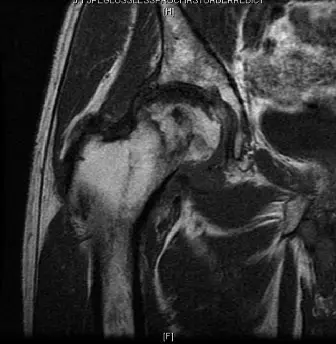

- في حالة المريض الذي استعرضناه، أكد الرنين المغناطيسي وجود نخر لاوعائي واسع النطاق في رأس الفخذ الأيمن (المرحلة الرابعة)، مع علامة الخط المزدوج وانهيار كبير تحت الغضروف.

الشكل 1: صورة رنين مغناطيسي قبل الجراحة للورك الأيمن تُظهر نخرًا لاوعائيًا واسعًا في رأس الفخذ (المرحلة الرابعة حسب فيكات-أرلت) مع علامة الخط المزدوج المميزة، وانهيار كبير تحت الغضروف، وتغيرات تنكسية مبكرة في الحُقّ.